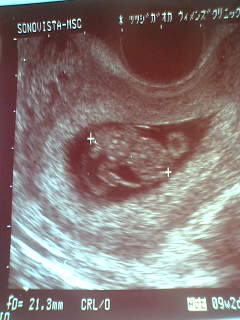

5/28 9週目の検診。

おかげで我が子は、お腹の中で丸々太っています(笑)

じゃなくて、順調に成長しています。

21mmになりました。

あんなに小さい点だったのに、もう2センチです。

ちゃんと、頭と胴体と手と足が解かる様になって

手や足をバタバタと動かしています。

とってもかわいい♪です。

このエコー写真を見たかっぱちゃんは、

「オレに似てる。」

と言っていました。(笑)